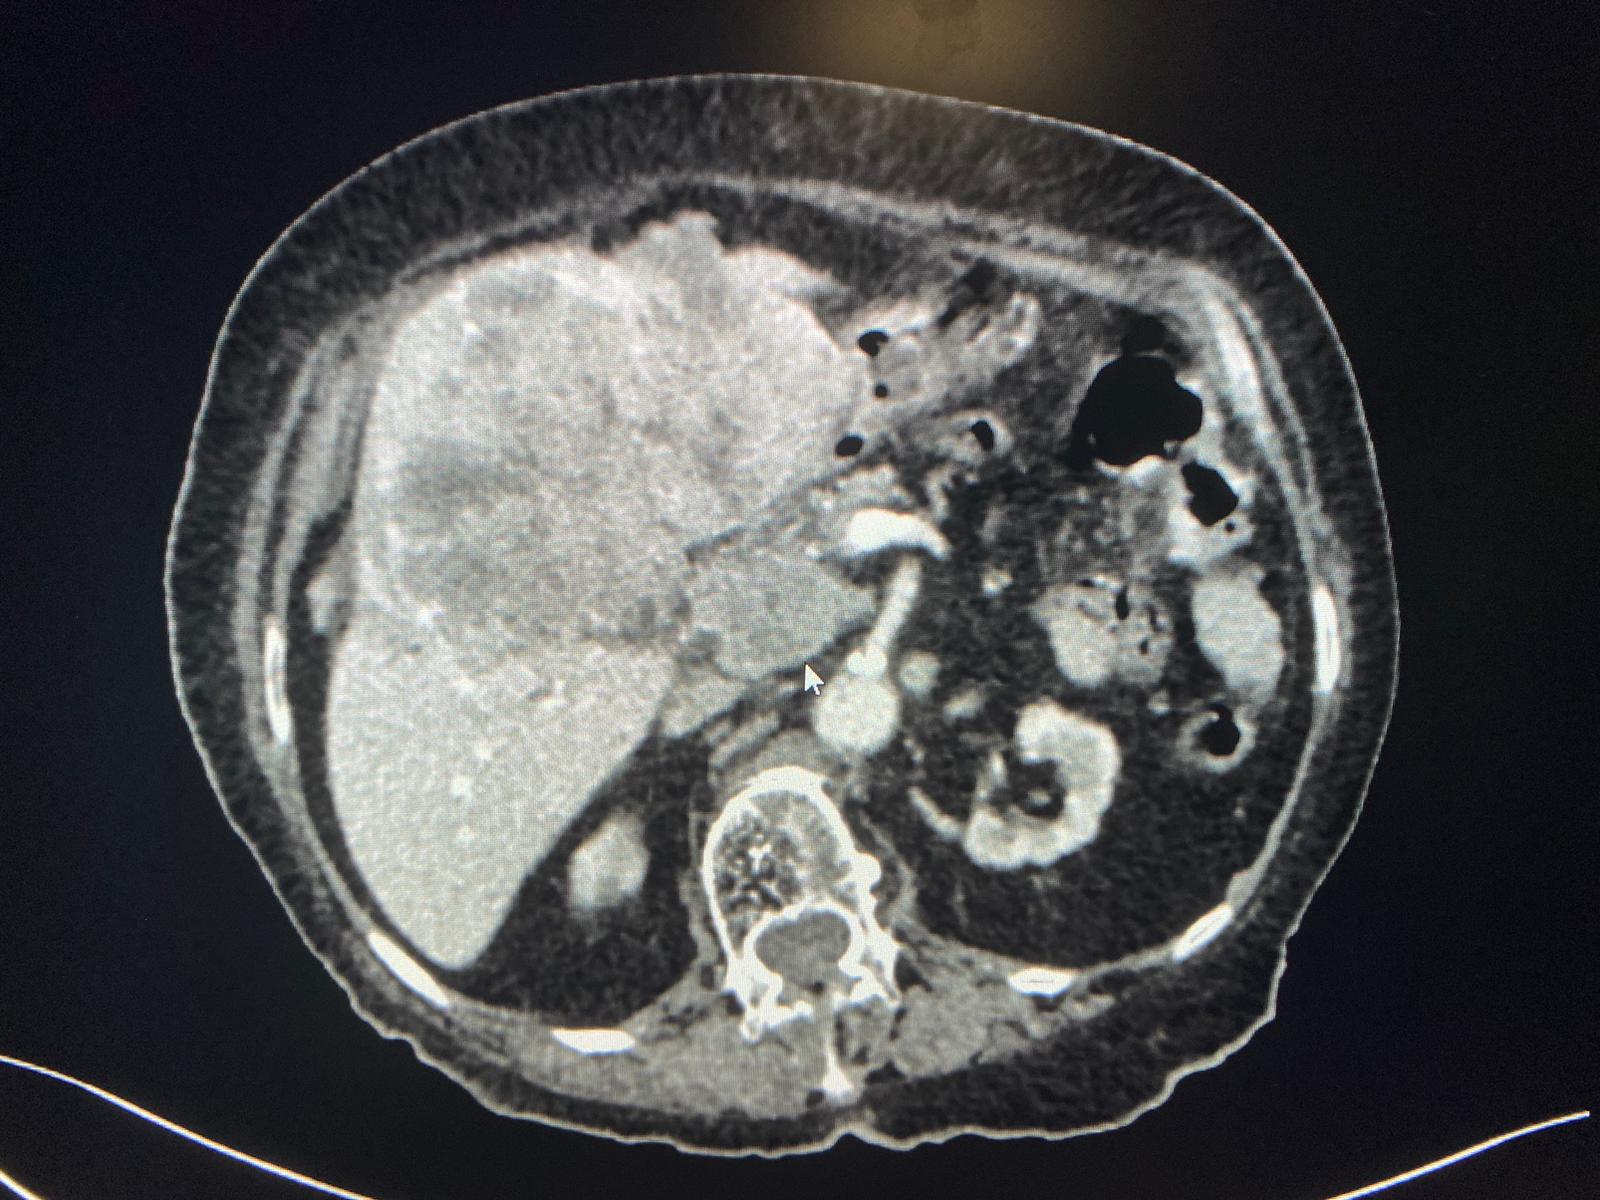

| Llaman por sospecha de colecisitis en mujer de 95 años. Se hace el TC y vemos una gran masa heterogènea hepática, que condiciona dilatación de via biliar intra y extra, junto con múltiples implantes perihepàticos, periportales, periesofágicos, intrapelvicos… Se sospecha de colangiocarcinoma, menos probable hepatocarcinoma. |